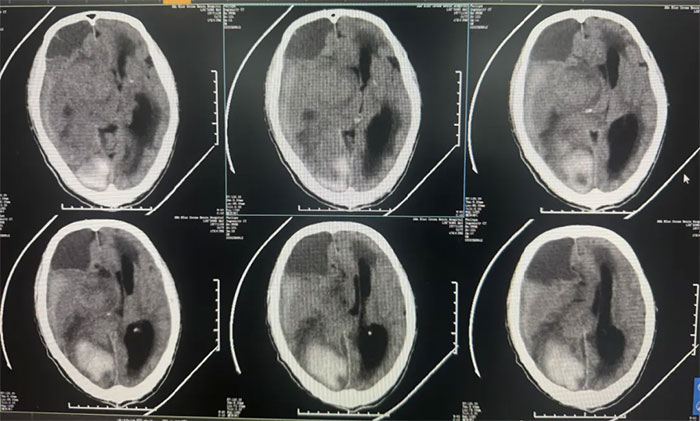

检查结果:

右顶枕叶出血,右侧额颞顶部亚急性硬膜下血肿,大脑镰下疝形成。